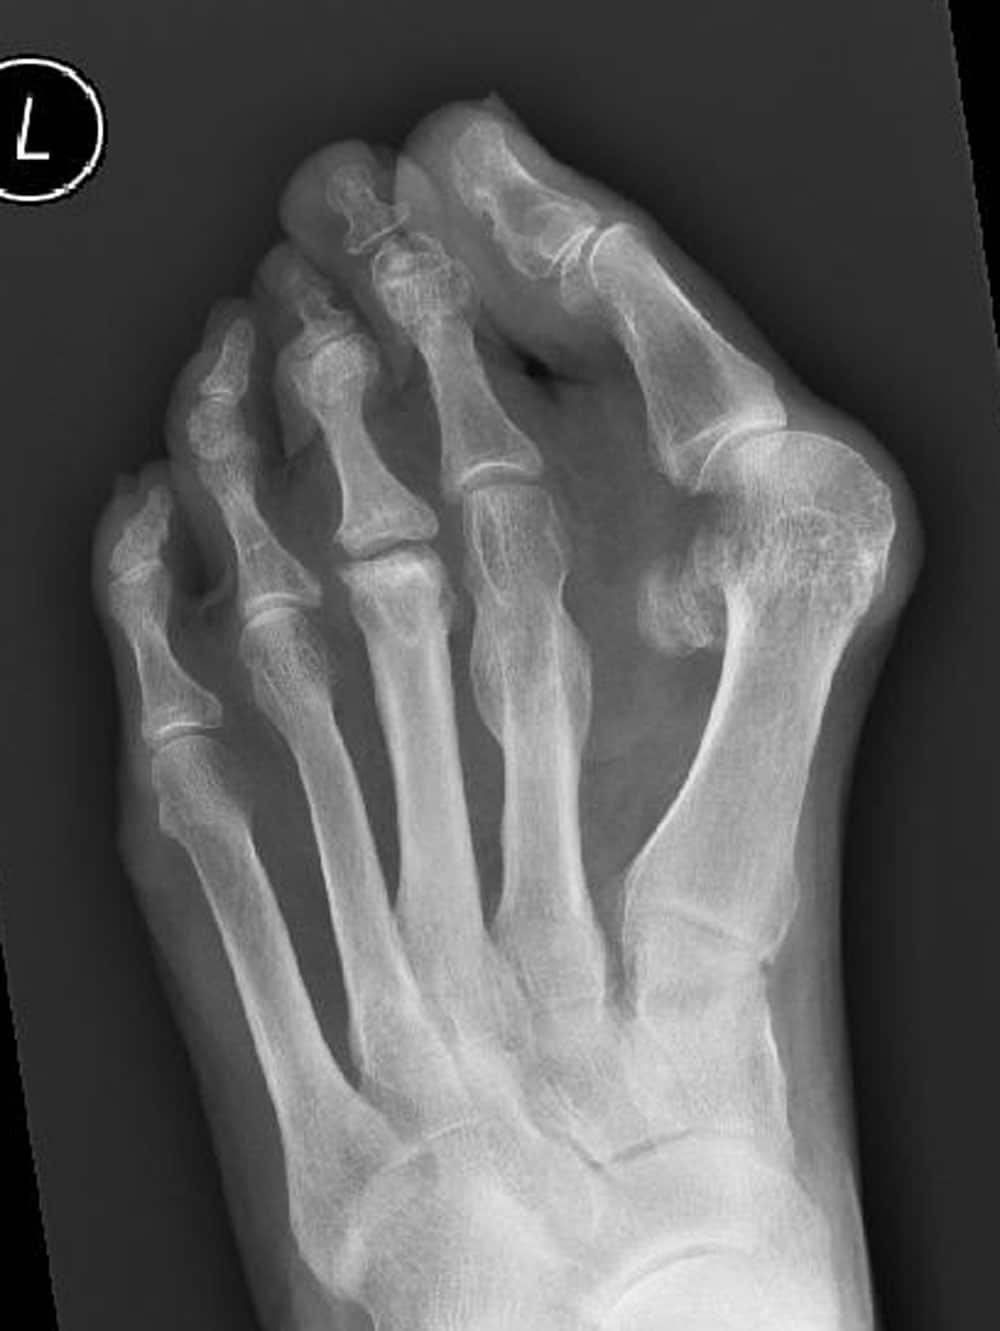

Eine Röntgen-Untersuchung des Fußes unter Belastung (im Stehen) gibt weitere wichtige Informationen zur Wahl der Operationsmethode. Eine gleichzeitige Großzehengrundgelenksarthrose ändert z.B. vollständig die Vorgehensweise. Verschiedene Winkel werden auf dem Röntgenbild gemessen, um das Ausmaß der Fehlstellung festzustellen. Dementsprechend können dann die operativen (invasiven) Techniken z.B. für einen schweren Hallux valgus angepasst werden. Das Vorhandensein eines Knick-Senkfußes muss auch in die operative Strategie mit einbezogen werden, dieser macht eine Korrektur notwendig.

Röntgen-Bild mit ausgeprägtem Hallux valgus. Man sieht eine Luxation des zweiten Grundgelenkes sowie eine Arthrose im Mittelfußbereich.